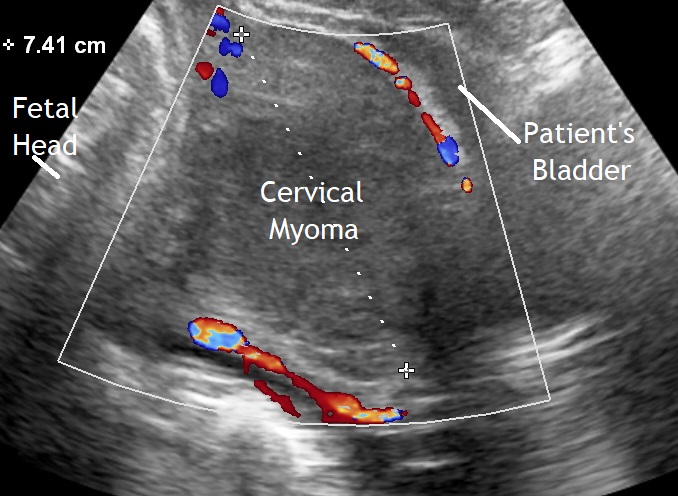

Our second image shows a myoma at the level of the uterine isthmus. On vaginal examination the fetal head could not be palpated. Here was a cesarean delivery performed with increased intraoperative bleeding.